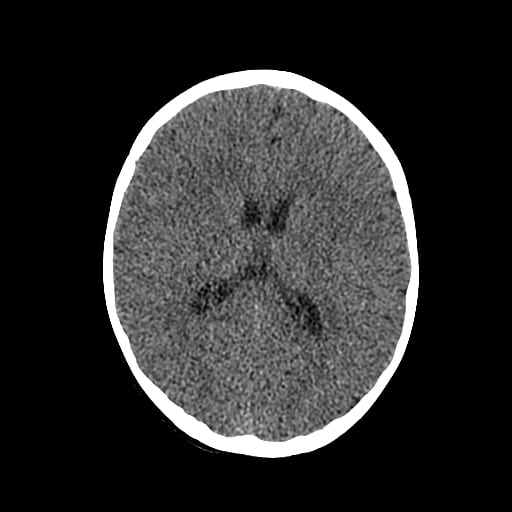

Age: 1

Sex: Male

Indication: Fall